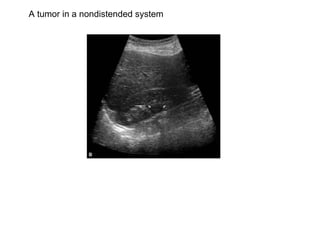

A tumor in a nondistended system